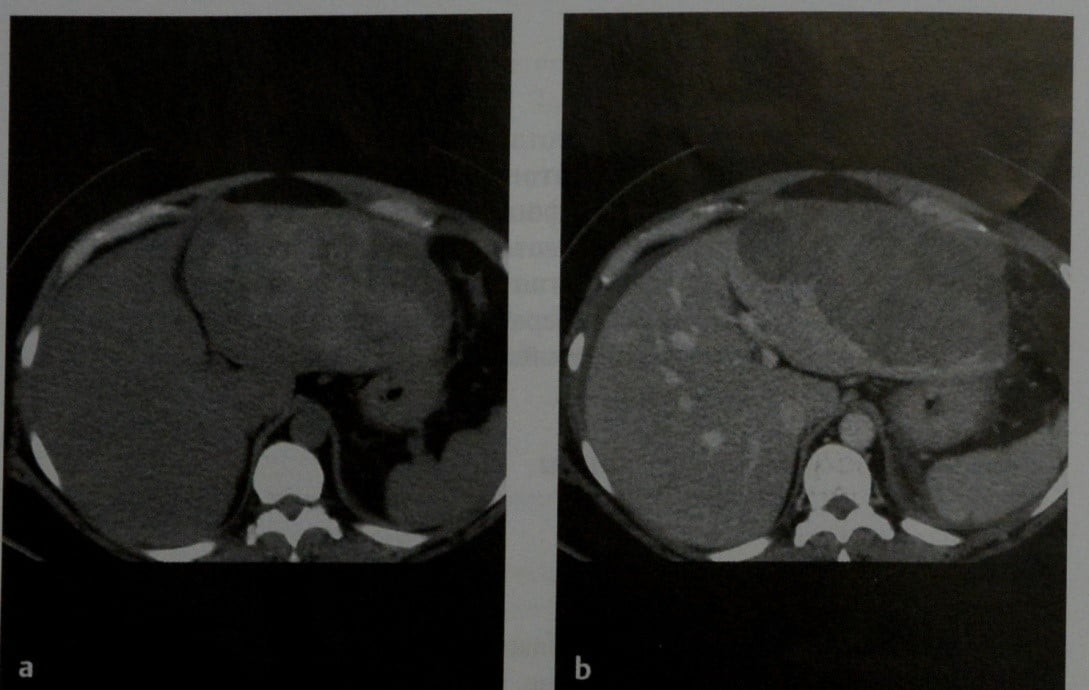

Методы динамического контрастирования печени на МРТ

Раздел: Снимки-подсказки